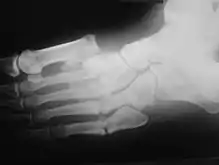

Radiologic findings

First, it is important to recognize that two types of abnormality may be detected. One is termed atrophic, in which there is osteolysis of the distal metatarsals in the forefoot. The more common form of destruction is hypertrophic joint disease, characterized by acute peri-articular fracture and joint dislocation. According to Yochum and Rowe, the "6 D's" of hypertrophy are:

- Distended joint

- Density increase

- Debris production

- Dislocation

- Disorganization

- Destruction

Atrophic features:

- "Licked candy stick" appearance, commonly seen at the distal aspect of the metatarsals

- Diabetic osteolysis

- Bone resorption